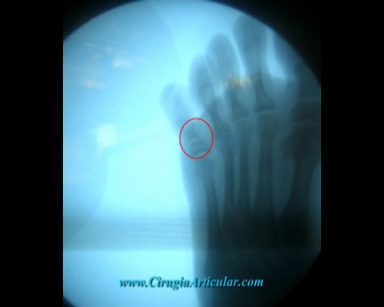

Siempre se controla mediante rayos – x los movimientos que realizamos con los instrumentos por debajo de la piel.

Foto 8

En la radiografía podemos ver como se ha realizado el corte de manera apropiada en el hueso.

Foto 9

Una vez realizada la corrección (línea roja). Se puede ver como cambia la orientación del dedo.